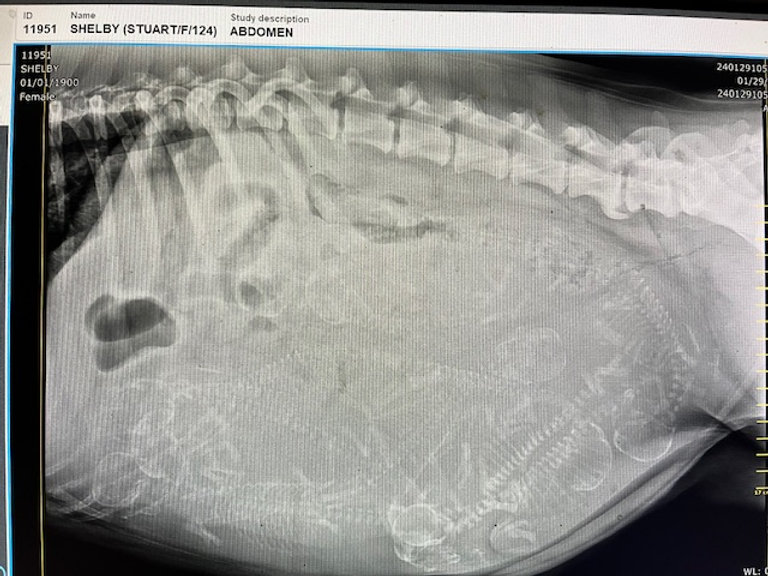

an x-ray of a dog

X-ray day is such an exciting day!!! We went for Shelby’s x-ray today and it looks like she has 8 (possibly 9) puppies. They all look great so now we “patiently” wait for them to arrive. Below is a picture of the x-ray.